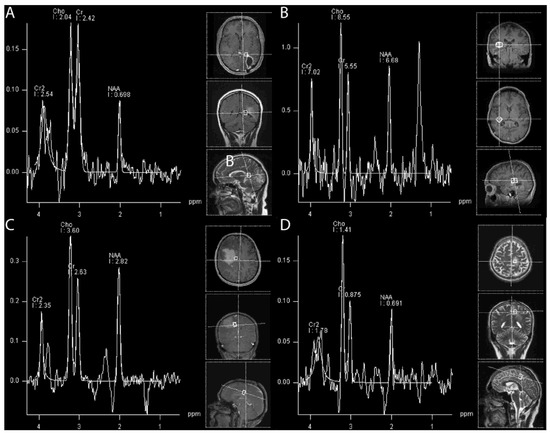

4.1.6. (1H) Magnetic Resonance Spectroscopy

- Sundgren, P.C. Mr Spectroscopy in Radiation Injury. AJNR Am. J. Neuroradiol. 2009, 30, 1469–1476. [Google Scholar] [CrossRef]

- Walecki, J.; Sokól, M.; Pieniążek, P.; Maciejewski, B.; Tarnawski, R.; Krupska, T.; Wydmański, J.; Brzeziński, J.; Grieb, P. Role of Short Te 1h-Mr Spectroscopy in Monitoring of Post-Operation Irradiated Patients. Eur. J. Radiol. 1999, 30, 154–161. [Google Scholar] [CrossRef] [PubMed]

- Amin, A.; Moustafa, H.; Ahmed, E.; El-Toukhy, M. Glioma Residual or Recurrence Versus Radiation Necrosis: Accuracy of Pentavalent Technetium-99m-Dimercaptosuccinic Acid [Tc-99m (V) Dmsa] Brain Spect Compared to Proton Magnetic Resonance Spectroscopy (1h-Mrs): Initial Results. J. Neuro-Oncol. 2012, 106, 579–587. [Google Scholar] [CrossRef] [PubMed]

- Rock, J.P.; Hearshen, D.; Scarpace, L.; Croteau, D.; Gutierrez, J.; Fisher, J.L.; Rosenblum, M.L.; Mikkelsen, T. Correlations between Magnetic Resonance Spectroscopy and Image-Guided Histopathology, with Special Attention to Radiation Necrosis. Neurosurgery 2002, 51, 912–919; discussion 919–920. [Google Scholar]

- Weybright, P.; Sundgren, P.C.; Maly, P.; Hassan, D.G.; Nan, B.; Rohrer, S.; Junck, L. Differentiation between Brain Tumor Recurrence and Radiation Injury Using Mr Spectroscopy. AJR Am. J. Roentgenol. 2005, 185, 1471–1476. [Google Scholar] [CrossRef]

- Galijasevic, M.; Steiger, R.; Mangesius, S.; Mangesius, J.; Kerschbaumer, J.; Freyschlag, C.F.; Gruber, N.; Janjic, T.; Gizewski, E.R.; Grams, A.E. Magnetic Resonance Spectroscopy in Diagnosis and Follow-up of Gliomas: State-of-the-Art. Cancers 2022, 14, 3197. [Google Scholar] [CrossRef] [PubMed]

- Grams, A.E.; Mangesius, S.; Steiger, R.; Radovic, I.; Rietzler, A.; Walchhofer, L.M.; Galijasevic, M.; Mangesius, J.; Nowosielski, M.; Freyschlag, C.F.; et al. Changes in Brain Energy and Membrane Metabolism in Glioblastoma Following Chemoradiation. Curr. Oncol. 2021, 28, 5041–5053. [Google Scholar] [CrossRef] [PubMed]